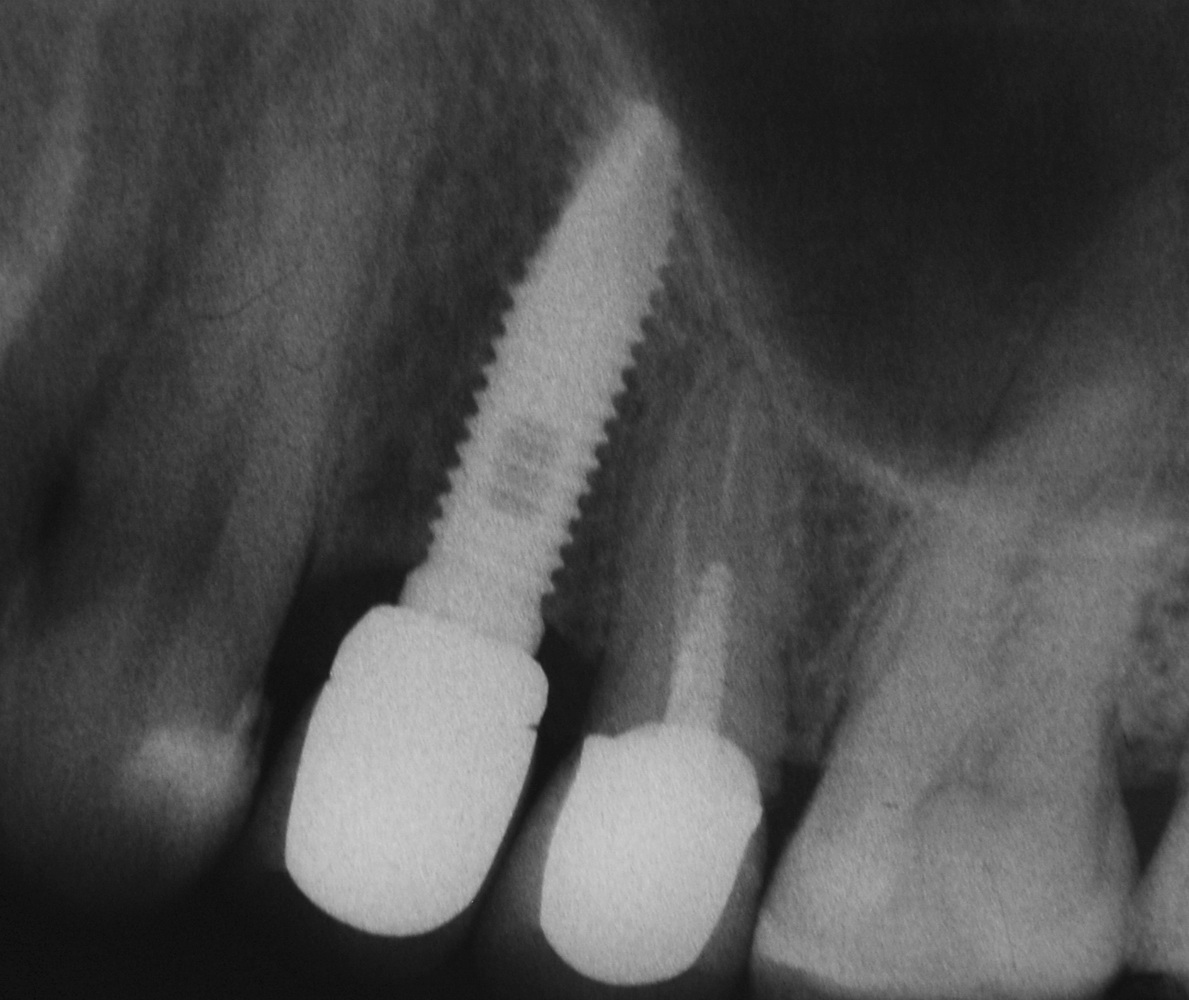

Оптимальное расстояние от дна гайморовой пазухи до верхней точки альвеолярного гребня верхней челюсти, при котором возможна стабилизация импланта длиной 10-11 мм – не менее 3-4 мм. Однако, в некоторых случаях имплантат длиной 11 мм удается стабилизировать в меньшем объеме костной ткани (рис 46, 47, 48):

Рисунок 46, 47, 48. Стабилизация импланта при толщине костной ткани менее 3 мм: слева – установка импланта после синуслифтинга, в центре – заполнение субантрального пространства спейсером, справа – рентгенологический контроль.